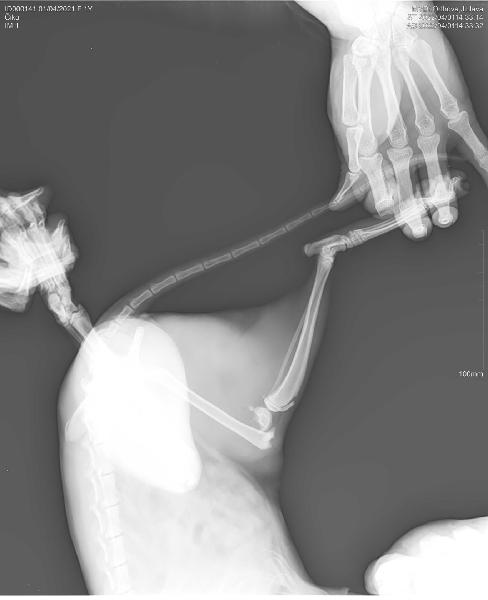

V pátek se nám domů vrátila naše kočka po třech nohách. Chuděra brečela bolestí, i když si lehla, bylo vidět jak ji to bolí... po vyšetření na veterině ji byla zjištěna zlomenina stehenní kosti. Pravděpodobně ji někdo pořádně nakopnul... :-( Jsem na rodičovské s dcerou, syn je v první třídě a peníze na operaci bohužel nemám. Do týdne by mělo být zoperováno, kočka je mladá (1 rok), ráda bych ji nohu zachránila. Levnější varianta je amputace nohy nebo ji nechat se zlomeninou. Našel by se někdo, kdo by kočičku finančně podpořil? Vše bychom zdokumentovali, uvedli kde bude operována, zveřejnili fakturu a případný přebytek peněz dali ostatním kočičkám co potřebují pomoc. Kočka je kastrovaná.